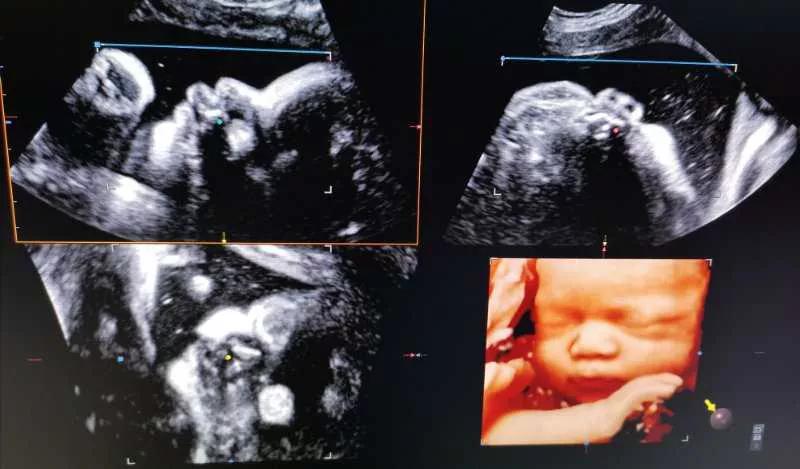

四维彩超不仅能够看到宝宝在妈妈肚子里的实时动态图像,还能够多方位、多角度的观察胎儿的生长发育情况,更是为早期诊断胎儿先天畸形,如:如唇腭裂,脑膜膨出,开放性脊柱裂等疾病提供准确的科学依据,为优生优育保驾护航。

四维彩超的最佳检查时间是20~26周 ,由于该时期胎儿的肢体和主要脏器已经基本发育,羊水量适中,胎儿活动度大,有利于成像和筛查,所以各位孕妈妈千万不要错过了哟!